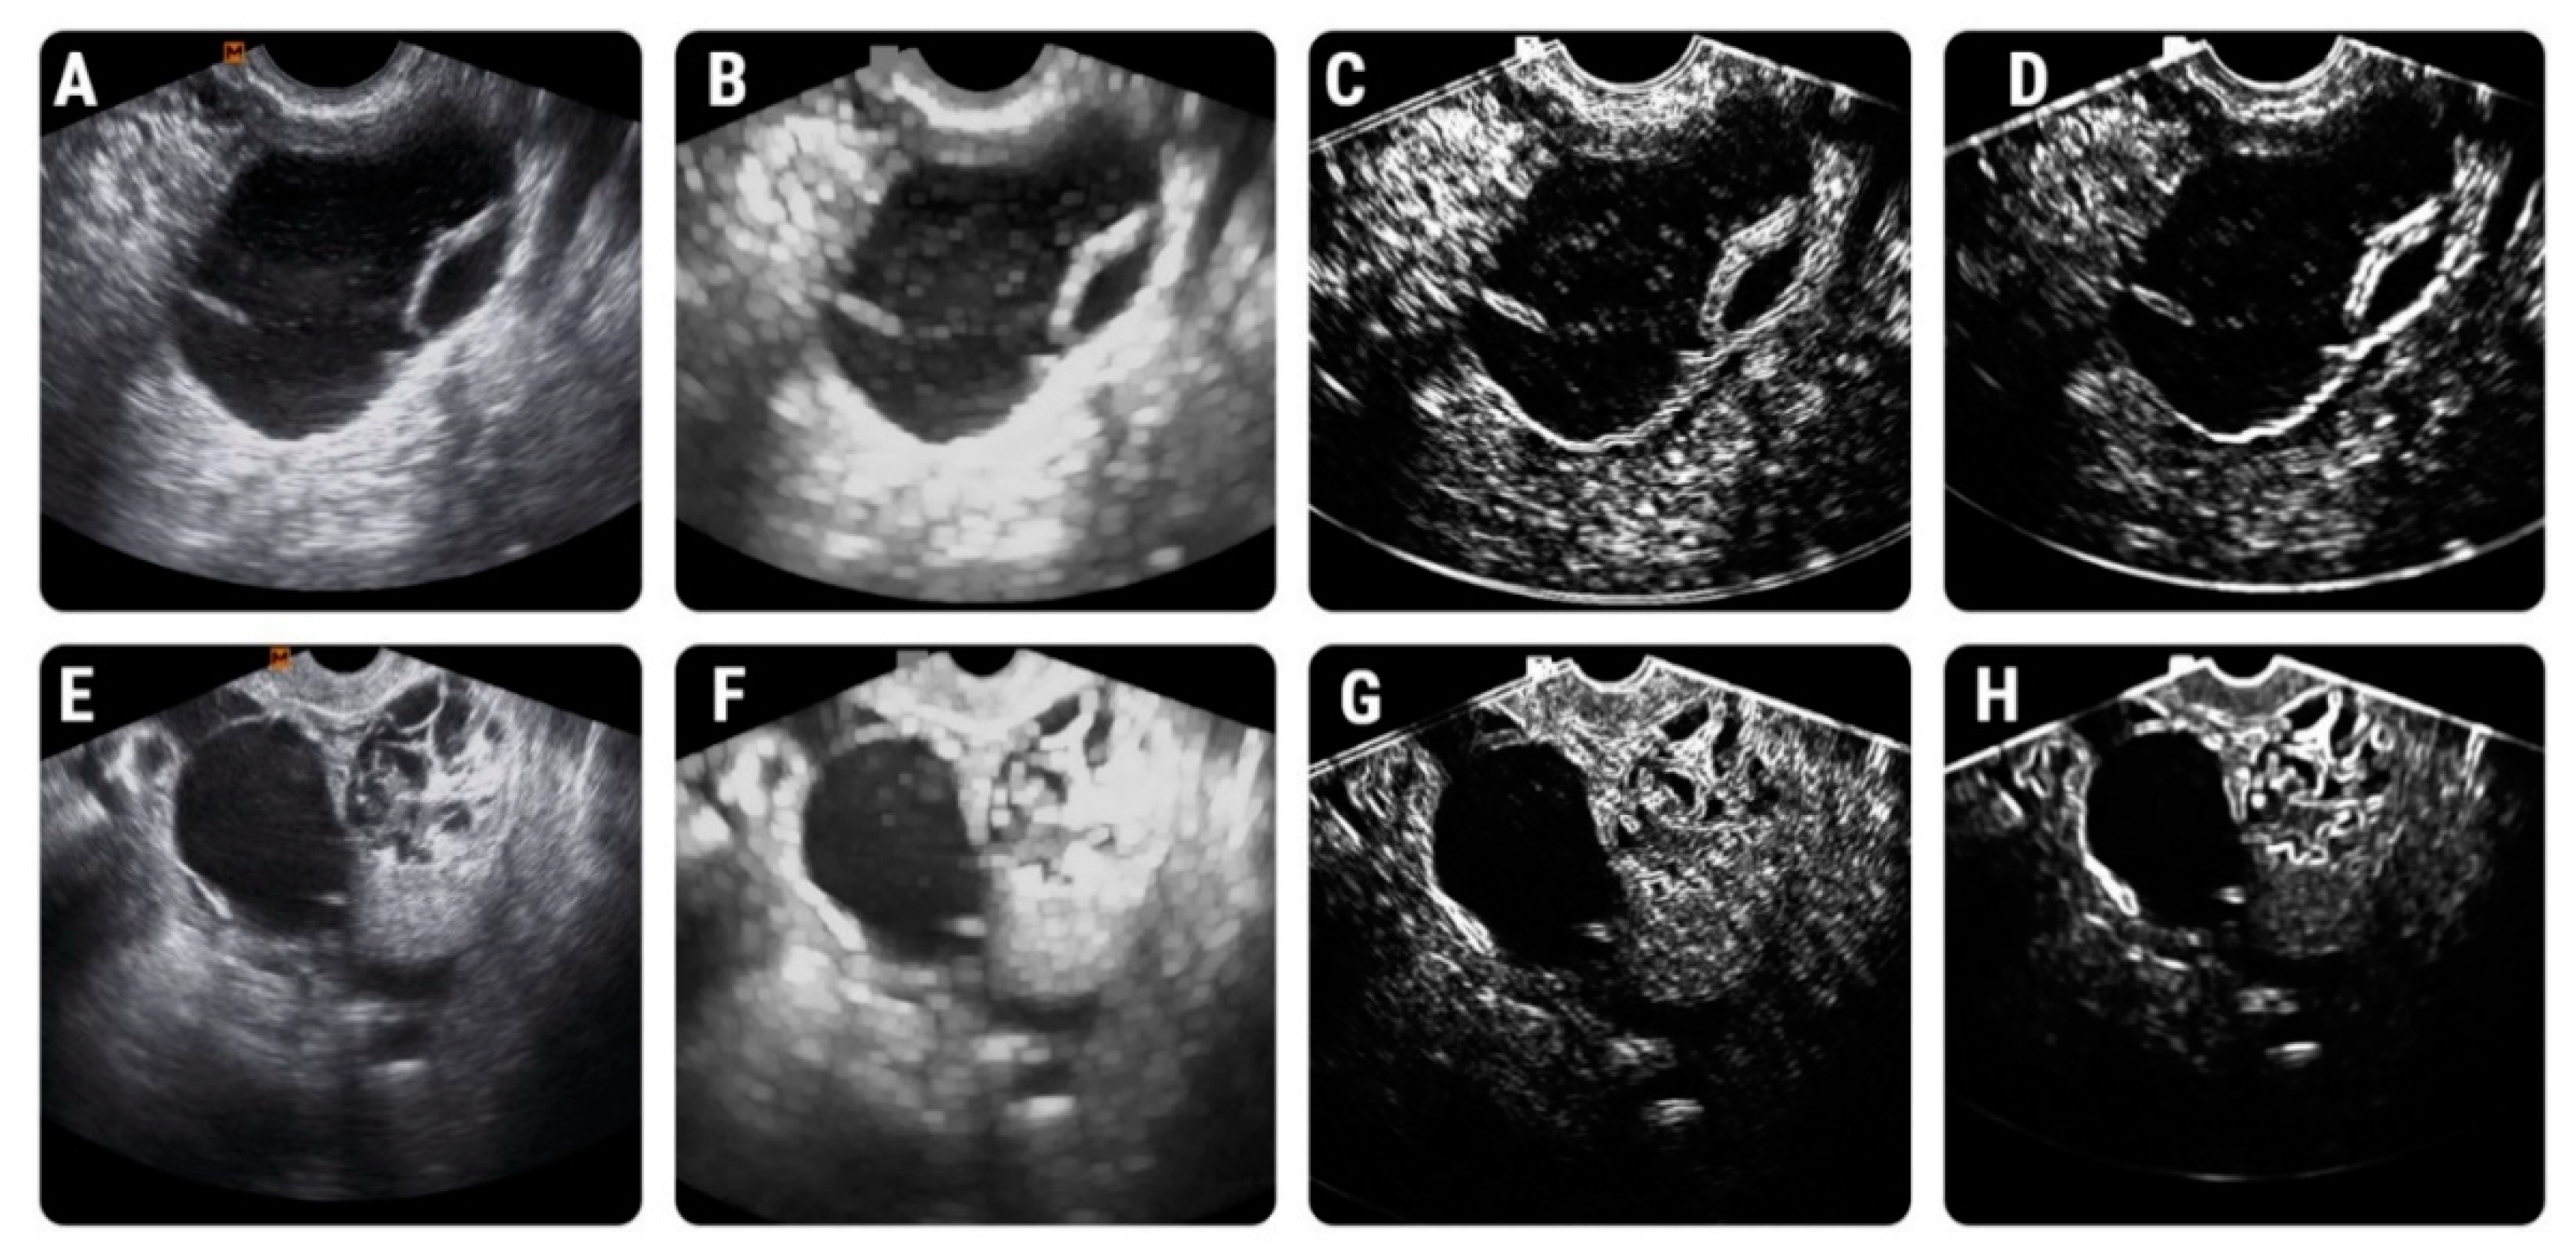

2.4.1. Image Pre-Processing and Segmentation